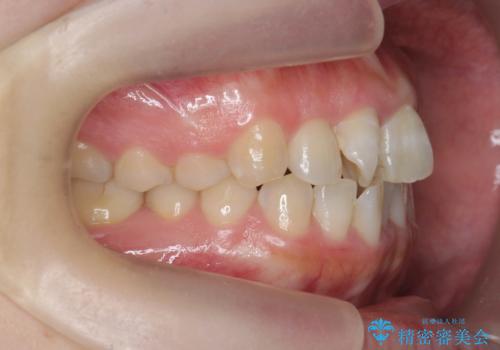

前歯のねじれをマウスピース矯正インビザラインで治療

- 長年気になっている、前歯のねじれの矯正治療を希望され来院されました。

十分にマウスピース矯正インビザラインで治療が可能と判断し、治療を進めることとしました。

長年気になっていた前歯のねじれが、ワイヤーをつけることなく矯正を行うことができ、大変喜んでいただくことができました。